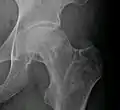

X-ray images of avascular necrosis in the early stages usually appear normal. In later stages it appears relatively more radio-opaque due to the nearby living bone becoming resorbed secondary to reactive hyperemia.[2] The necrotic bone itself does not show increased radiographic opacity, as dead bone cannot undergo bone resorption which is carried out by living osteoclasts.[2] Late radiographic signs also include a radiolucency area following the collapse of subchondral bone (crescent sign) and ringed regions of radiodensity resulting from saponification and calcification of marrow fat following medullary infarcts.

Radiography of avascular necrosis of left femoral head. Man of 45 years with AIDS.